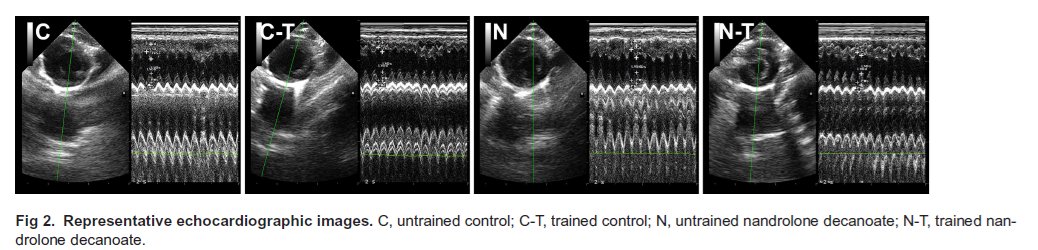

| Plos One |

Combined nandrolone and resistance training induced cardiac remodelling and oxidative stress despite enhanced cardiomyocyte contractility

doi.org/10.1371/journa…

English